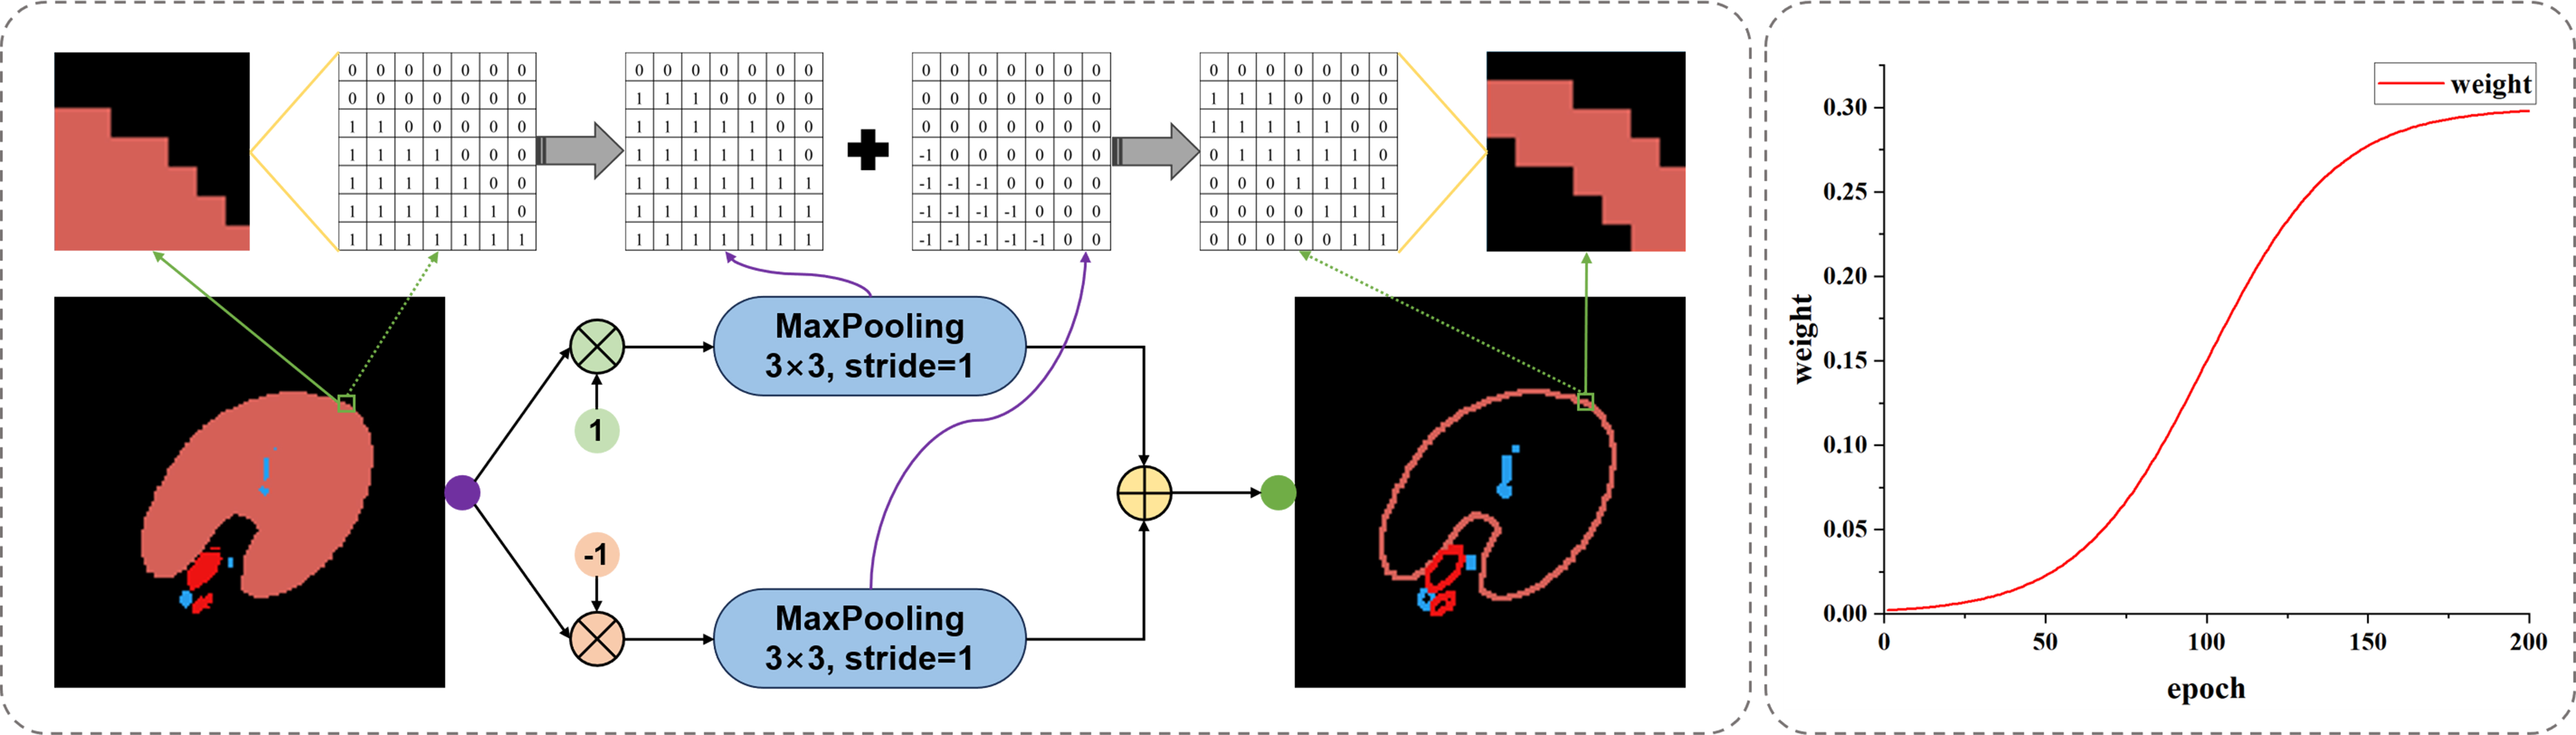

3.4. The contour loss that can reduce class imbalance and the loss strategy

In order to target slender structures and weaken the influence of internal areas in ordinary classification structures, we designed contour loss LContour as given in Equation (5), which simplifies the classification results of all structures into contour labels. The calculation of contours depends on a maximum pooling function (MP) with a window size of 3 × 3 and a step size of 1. By calculating the MP results of positive and negative samples of the labels and summing them up, as shown in Figure 7, we effectively extract the classification edges of various types of segmented images and reduce the computational imbalance caused by too many internal pixels in the structures. By dividing the contour difference F norm between the true label and the predicted label by the F norm of the true label contour, we obtain a global contour error result.

where G represents the true value label, and P represents the predicted label. In addition, our total loss consists of three parts, including Dice loss LDice, Cross Entropy loss LCE, and Contour loss, as given in

It cannot be ignored that contour loss lacks directionality, which may bring significant uncertainty to the network in the early stages of training. Due to the above reason and the poor performance of the cross-entropy loss function in class imbalance situations, weights α and β are respectively set for the two, where α is set to 0.8 and β is set to

The variation of β during the training process is shown in the coordinate graph on the right side of Figure 7. Throughout the entire training process, the maximum value of β is 0.3, and it follows a pattern of slow growth, accelerated growth, and finally stable growth. This is because in the initial training process, the network is underfitting, and the predicted contour has a large degree of uncertainty. After the network reaches a certain segmentation ability, the weight is increased to optimize the segmentation contour.